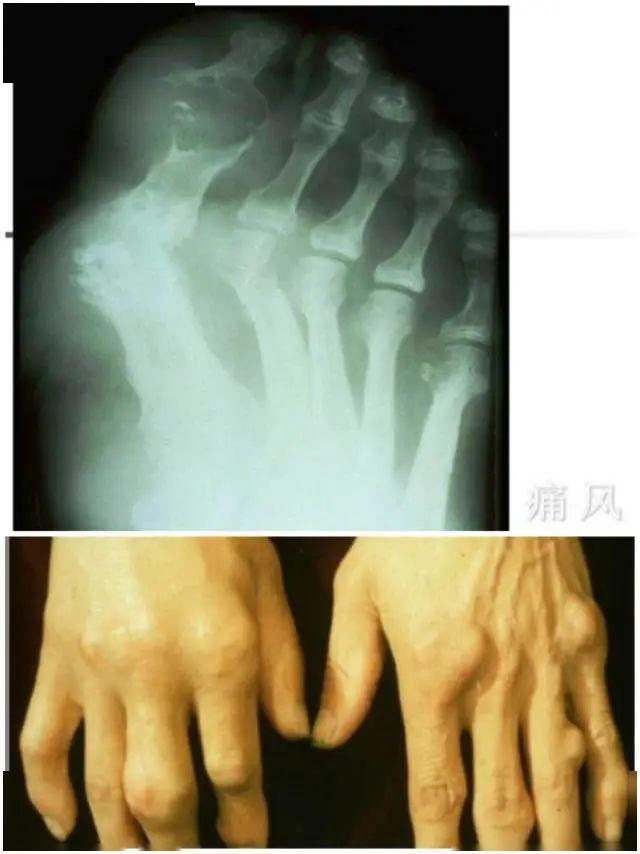

临床表现:

急性期:60%-70%首发于拇趾跖关节,重复发生逐步影响多个关节,大关节劳累时可有关节积液。终究构成关节变形。

夜间或清晨,通常在几小时内到达高峰,常不能被触及,皮肤发红发亮,并会导致脱屑,可伴发热、头痛等症。

缓慢期:痛风石构成,症状不完全缓解。